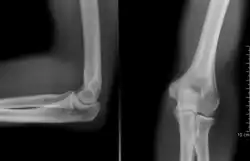

radiographie (coude droit)

Coude gauche